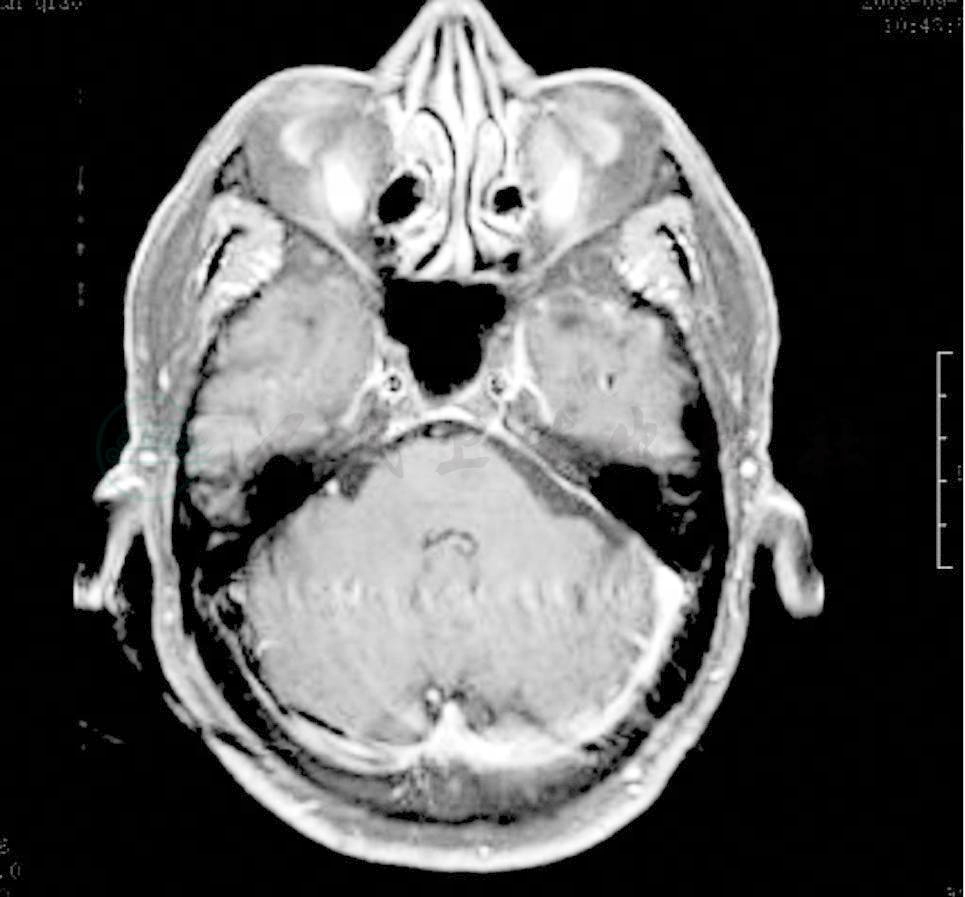

(2009-7-9)鼻咽MRI平扫+增强(图1)。

图1 鼻咽MRI

①鼻咽顶部左侧饱满,黏膜线粗糙,增强呈片状明显强化,鼻咽部病变,建议活检;②左侧海绵窦旁,岩骨旁、小脑天幕处脑膜明显增厚并强化;③左侧乳突炎